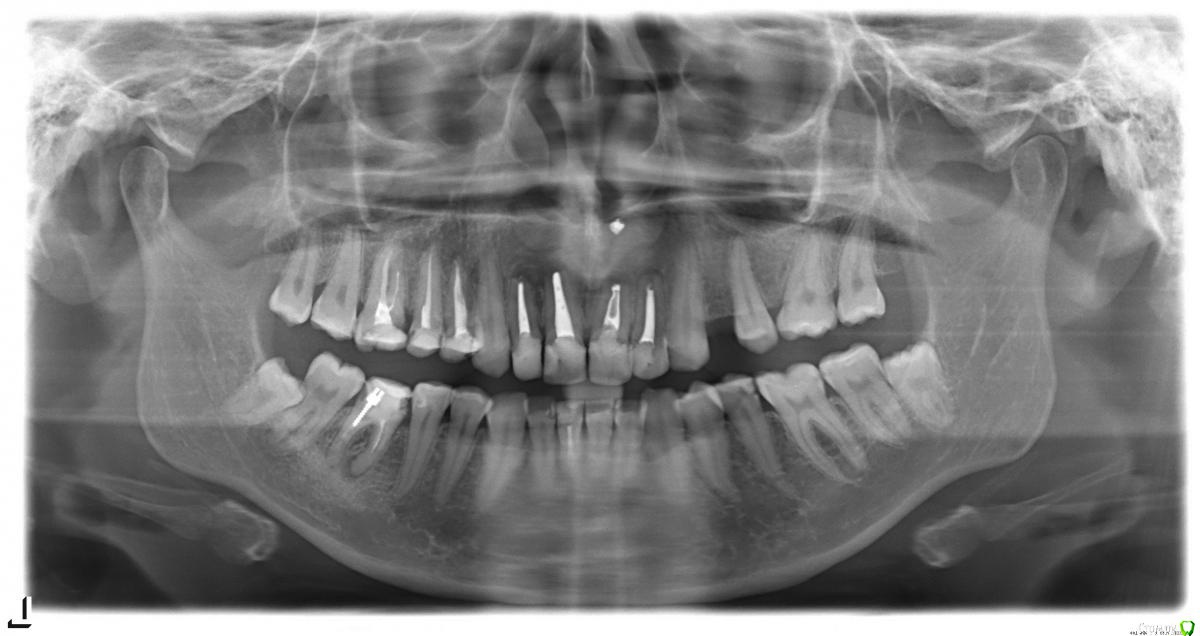

Анна 1986 Опубликовано 18 мая, 2015 Поделиться Опубликовано 18 мая, 2015 (изменено) Добрый день!История такая: под вопросом перелечивание каналов с кистами, самый актуальный сейчас зуб - это шестерка (снизу слева). Стоит ли пытаться перелечить (насчитали очень дорого, и без каких-либо гарантий) зуб, есть ли шанс, что киста "пройдет", или в этом случае лучше удалить зуб и поставить мост (за два соседних)? Еще конечно под вопросами и перелечивание всех остальных зубов с кистами (их насчитали аж 3), передние 4 зуба месяц назад удалили (планирую ставить мост, т.к. очень боюсь что наращивание костной ткани и имплантация пройдут не удачно). Заранее спасибо, всем кто откликнется! Прикладываю ссылку на заархивированную КТ https://yadi.sk/d/cH63onEggiLwU Изменено 18 мая, 2015 пользователем Анна 1986 Ссылка на комментарий

Анна 1986 Опубликовано 18 мая, 2015 Автор Поделиться Опубликовано 18 мая, 2015 еще есть оптг Ссылка на комментарий

Bier Опубликовано 19 мая, 2015 Поделиться Опубликовано 19 мая, 2015 у меня получается какой-то замкнутый круг(((делать наращивание костной ткани боюсь: что не приживется, что потребуется повторное наращивание, что образуется киста (ранее над передними зубами кисты появлялись 5 раз, делали резекции, в следствии чего от своего костного материала почти ничего не осталось)Имплантация тоже не 100% гарантия приживаемости.Если хотя бы гарантия была, что все точно приживется - еще бы наверно рискнула, а так очень страшно. Конечно огромную роль играет финансовая сторона, за наращивание около 80 т.р., за каждый имплантат (а их надо 5) от 80 т.р. (80+5*80=480 тыс.), и это если с перового раза все приживется. плюс перед этим перелечить все имеющиеся зубы - просто неподъемная на сегодняшний день для меня сумма. С мостом - я тоже понимаю, что пострадают (или вообще со временем потеряю) родные здоровые зубы (практически последние здоровые), но ведь он, как я понимаю, точно "приживется". Конечно еще есть третий вариант - съемник, но это просто морально тяжело, в 30 лет остаться со съемным протезом (несмотря на то что это самый бюджетный и безболезненный вариант)С тем уровнем лечения каналов, что есть на Ваших снимках , мост - путь в никуда. Для фронтальной зоны надо всего 2 имплантата. Есть места, где делают все с гарантией. Подумайте о том, чтобы сделать операцию в другом городе. Ссылка на комментарий

Alejandro Опубликовано 20 мая, 2015 Поделиться Опубликовано 20 мая, 2015 Зуб скорее всего резорциненный, успех перелечивания во многом будет зависеть от уровня мастерства доктора. Ссылка на комментарий